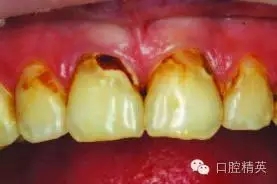

術(shù)前圖1a:患者主訴上前牙齲壞

患者主述上前牙齲壞(圖1a)?;颊叻裾J(rèn)不適癥狀,僅是因?yàn)榘l(fā)現(xiàn)其外觀變化了。

檢查發(fā)現(xiàn),上前牙有V類洞和III類洞得齲壞。

局部麻醉后,先行右上中切牙去腐備洞。使用排齦線暴露齦下齲壞。

使用330-鎢鋼車針去除尖銳和薄弱的牙釉質(zhì)邊緣,開敞釉質(zhì)洞緣(圖2)。